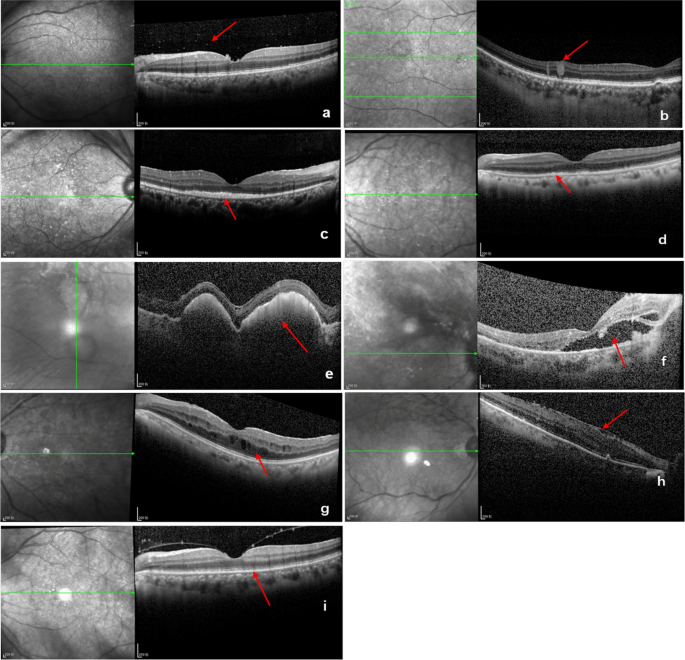

SD-OCT images were used to evaluate the following features: vitreous cells (dense particles in the posterior vitreous) (Fig. 1a), intraretinal infiltration (hyperreflective lesions within the neuroretina), (Fig. 1b), subretinal infiltration (hyperreflective lesions between neurosensory retina and RPE), (Fig. 1c), retinal pigment epithelium (RPE) abnormalities (irregularity and hyperreflective nodules of the RPE) (Fig. 1d), RPE detachment (PED) (nodular deposits between the RPE and Bruch membrane) (Fig. 1e), subretinal fluid (Fig. 1f), macular edema (Fig. 1g), epiretinal membrane (ERM) (Fig. 1h), disruption of the ellipsoid zone (Fig. 1i). All SD-OCT images were analyzed by two independent observers blind to the experimental conditions. Ultra-widefield fundus photography and FAF imaging were performed. Complete remission was defined as the absence of cells in the vitreous and the resolution of retinal or RPE infiltrates. Relapse was defined as the re-appearance of vitritis and retinal or RPE infiltrates [37].

Representative SD-OCT images displaying characteristic features of PVRL. a vitreous opacities (arrow) b intraretinal infiltration (arrow) c subretinal infiltration (arrow) d retinal pigment epithelium (RPE) abnormalities (hyperreflective nodules or irregularity) (arrow) e RPE detachment (arrow) f subretinal fluid (arrow) g macular edema (arrow) h epiretinal membrane (arrow) i disruption of the ellipsoid zone (arrow)